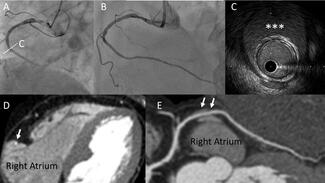

An 80-year-old man was referred to our cath-lab for transcatheter aortic valve implantation (TAVI) due to symptomatic severe aortic valve stenosis. The intervention utilized a balloon-expandable prosthesis (Edwards Sapien 3 Ultra n°26,...